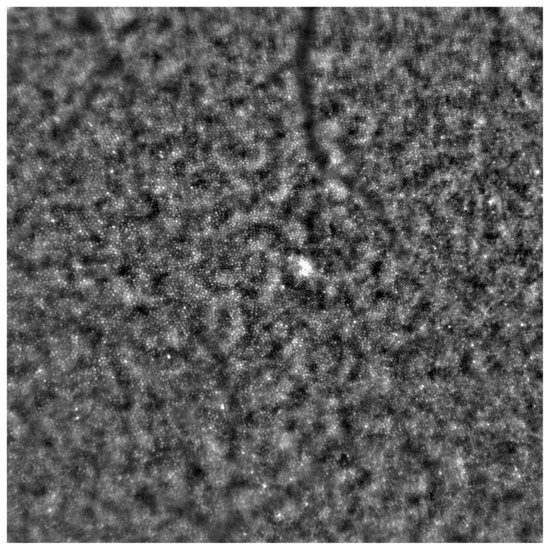

- Samelska, K.; Kupis, M.; Zaleska-Żmijewska, A.; Szaflik, J.P. Adaptive optics imaging in the most common inherited retinal degenerations. Klin. Ocz. 2021, 123, 74–79. [Google Scholar] [CrossRef]

- Gill, J.S.; Moosajee, M.; Dubis, A.M. Cellular imaging of inherited retinal diseases using adaptive optics. Eye 2019, 33, 1683–1698. [Google Scholar] [CrossRef]

- Zaleska-Żmijewska, A.; Wawrzyniak, Z.M.; Ulińska, M.; Szaflik, J.; Dąbrowska, A.; Szaflik, J.P. Human photoreceptor cone density measured with adaptive optics technology (rtx1 device) in healthy eyes: Standardization of measurements. Medicine 2017, 96, e7300. [Google Scholar] [CrossRef]

- Zaleska-Żmijewska, A.; Wawrzyniak, Z.M.; Dąbrowska, A.; Szaflik, J.P. Adaptive Optics (rtx1) High-Resolution Imaging of Photoreceptors and Retinal Arteries in Patients with Diabetic Retinopathy. J. Diabetes Res. 2019, 2019, 9548324. [Google Scholar] [CrossRef]